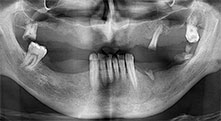

Implants

The four implants are in situ, as planned. The distal maxillary molars can still be used to fix the lined denture, which was introduced one month after implantation.